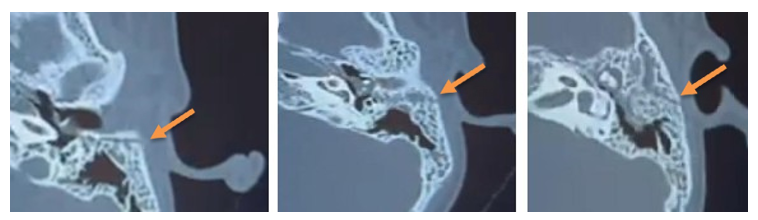

Impedance audiometry demonstrated an absent stapedial reflex on the affected side, suggesting a proximal lesion. High-resolution computed tomography (CT) of the temporal bone revealed a longitudinal fracture of the left petrous portion with an associated ipsilateral subdural haematoma and pneumocephalus deemed non- surgical.

Figure 2: Axial CT scan of the temporal bone showing a simple transverse fracture line of the petrous portion of the temporal bone, sparing the otic capsule, with haemorrhagic opacification of the tympanic cavity and mastoid air cells

Electro-neuromyography (ENMG) performed ten days post- trauma showed severe axonotmesis with more than 70% axonal loss.

Based on the imaging findings and the severity of the electrophysiological lesion, surgical exploration was performed through a transmastoid approach one month after the trauma. A cortical mastoidectomy was first performed, followed by an antro-atticotomy to expose the short process of the incus, a key landmark for identifying the facial nerve. A wide posterior tympanotomy was then carried out, allowing decompression of the facial nerve at the level of its genu and mastoid segment. Intraoperative findings revealed a severely contused facial nerve at the second genu, consistent with axonotmesis, while neural continuity was preserved. Decompression of the tympanic and mastoid segments was achieved, and a temporalis fascia graft was interposed to protect and support the injured segment.

Figure 3: Per-operative image showing decompression of the facial canal at its second genu using a diamond burr

Figure 4: Per-operative image showing the appearance of the facial nerve after decompression

Figure 5: Per-operative image showing two aponeurotic grafts at the genu and the mastoid (third) segment of the facial nerve, through the posterior tympanotomy, the round window niche, the pyramidal eminence, and the stapes tendon were clearly visualized